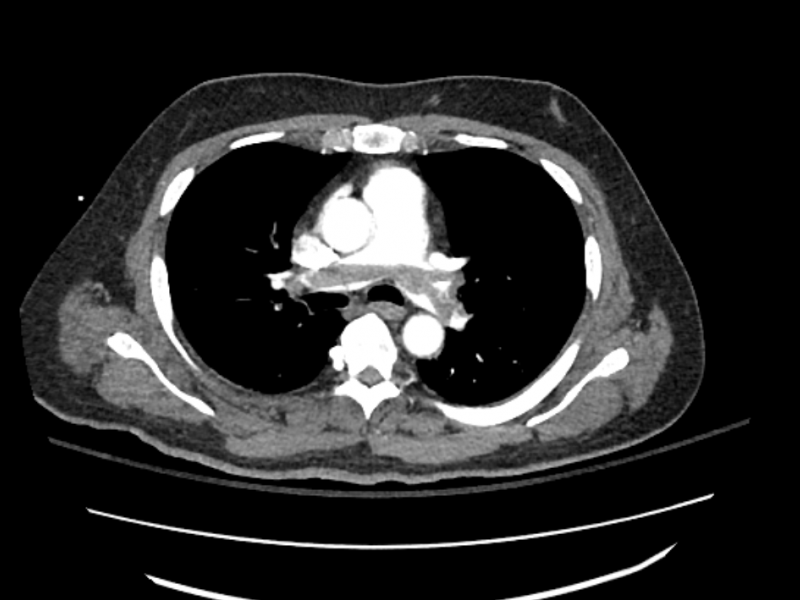

A 75 yo F w/ a history of HTN, smoking presents to the ED w/

A 45 yo male presents after syncope in rehabilitaion center